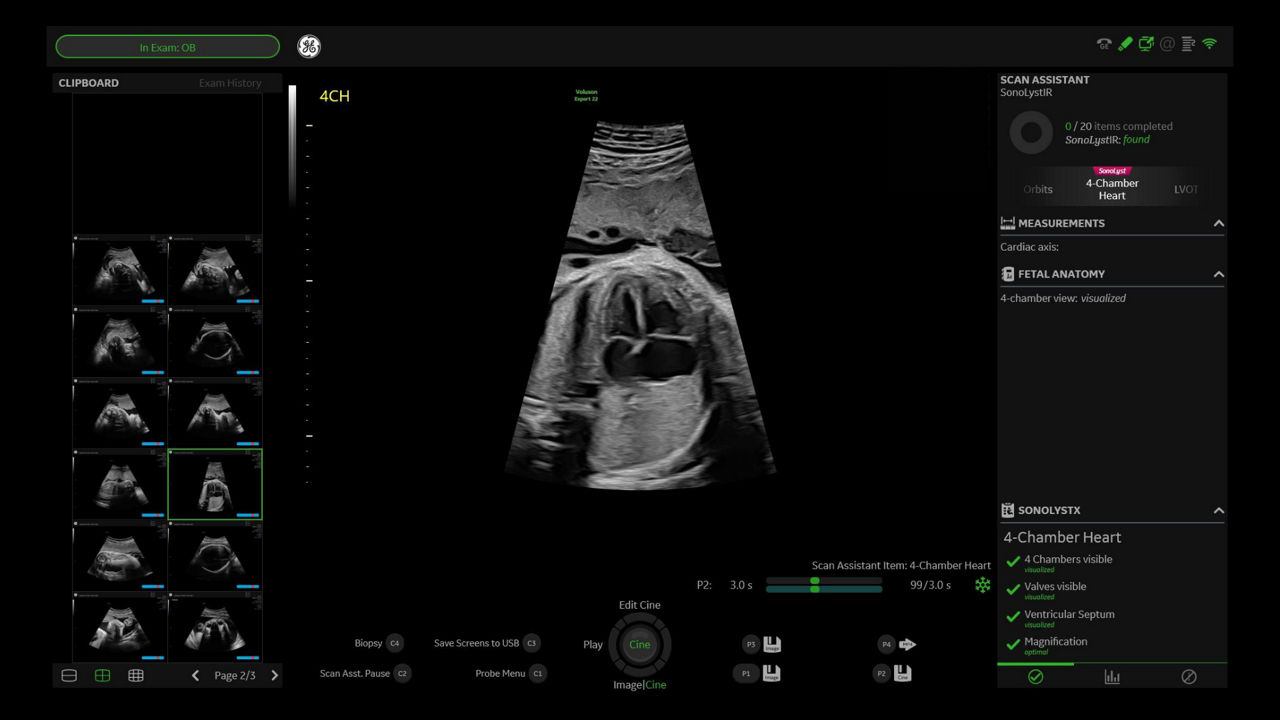

SonoLyst

AI tool helps automatically identify fetal anatomy.

Developed by: GE HealthCare - Voluson™